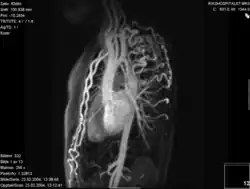

- Die Magnetresonanztomografie (=Kernspintomografie, MRT, NMR) ermöglicht eine gute Darstellung der ISTA. Durch die Flussmessungen ist eine Gradientenabschätzung möglich und gleichfalls eine 3-D-Rekonstruktion durchführbar.

- Mit der Spiral-Computertomografie ist gleichfalls eine 3-D-Rekonstruktion möglich.

Die beiden zuletzt genannten Untersuchungsmethoden dienen der anatomischen Rekonstruktion bei zusätzlich vorliegenden Aortenbogenfehlbildungen bzw. Variationen.

Koarktation der Aorta mit verschiedenen bildgebenden Verfahren:

D – MR 3D-kontrastverstärktes Angiogramm mit großem Pseudoaneurysma (Pfeilspitze) nach vorheriger plastischer Operation Angioplastie. Auf der Rückseite ist echtes Licht zu sehen (Pfeil)[11]